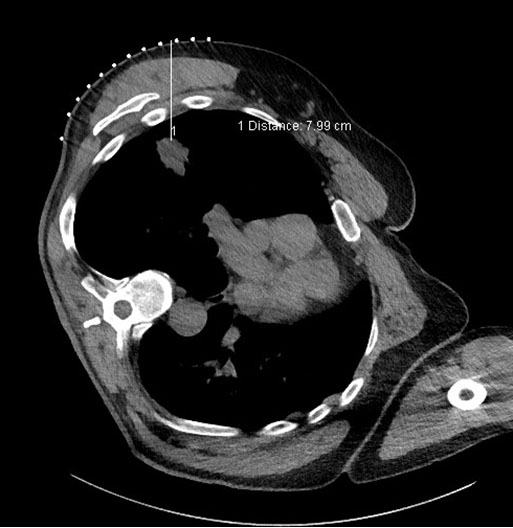

The suspicious lung nodule was further worked up with a bronchoscopy with biopsy. There was notable distortion in the right middle lobe, however, the transbronchial brushings and right middle lobe lavage did not reveal any malignant cells or infection (Figure 3). To exclude pulmonary malignancy, a positron emission tomography (PET) scan was conducted (Figure 4). The spiculated lesion was detected in the posterior segment of the right upper lobe with an increased tracer uptake with a maximum standardized uptake value (SUVmax) of 11.71, which was highly suspicious for malignancy. A repeat CT-guided biopsy was performed in the right upper lobe and the histopathological assessment identified mixed chronic active inflammation with an aggregate of filamentous microorganisms with sulfur granules of Actinomyces and no malignant cells (Figure 5) and (Figure 6).

Figure 5: CT-guided biopsy 18-gauge core axial needles were inserted into the mass in the right upper lobe of lung to obtain three cores. Postprocedure biopsy site was sealed with gel foam.